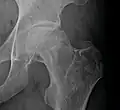

Radiography of avascular necrosis of left femoral head. Man of 45 years with AIDS.